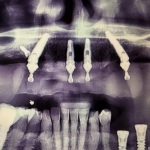

Cas clinique du Dr. Denglos avec les implants Co-axis®

La situation initiale montre un édentement complet bi-maxillaire avec axes implantaires défavorables et volumes osseux limités, compromettant la réalisation d’une réhabilitation implanto-portée transvissée sans correction d’angulation.

Avec la collaboration du Dr. Carl Denglos